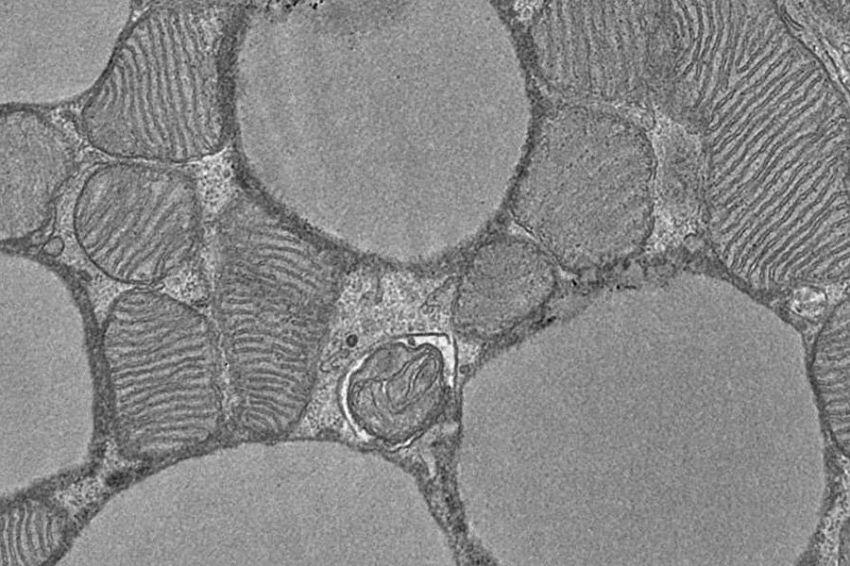

Мини-сердца созданы из человеческих плюрипотентных стволовых клеток (hPSC). Это клетки с особыми свойствами: они могут неограниченно размножаться в культуре и образовывать любой тип клеток. С помощью биологических или химических сигналов, встроенных в гидрогелевую матрицу, hPSC можно контролировать таким образом, что трехмерные клеточные агрегаты развиваются в сердечные органоиды за 10–14 дней. Это не скопления клеток сердечной мышцы, а сложные структуры, состоящие по меньшей мере из семи различных, четко структурированных типов клеток и тканей.

Как и в естественном эмбриональном развитии , искусственное мини-сердце состоит из трех чашеобразных слоев и включает зачаток сердца, предшественников печени и легких, а также кровеносных сосудов.

«Теперь мы адаптировали наш протокол дифференциации, то есть наши специальные экспериментальные инструкции, и добавили плотный эндотелиальный слой к сердечному органоиду, который выстилает кровеносные сосуды и из которого появляются кроветворные клетки и клетки-предшественники», — объясняет соавтор исследования Мириана Дардано. «Это первая в своем роде модель человеческого органа, которая объединяет все ткани в соответствии с развитием в эмбрионе».